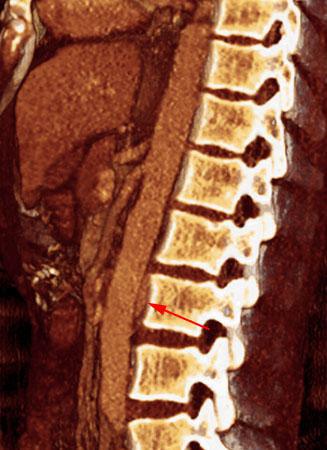

Trombosis venosa renal